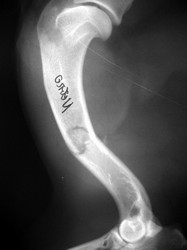

Fijación Externa

PRÁCTICAS CURSO DE FIJACIÓN EXTERNA PERFECCIONAMIENTO.

Húmero.